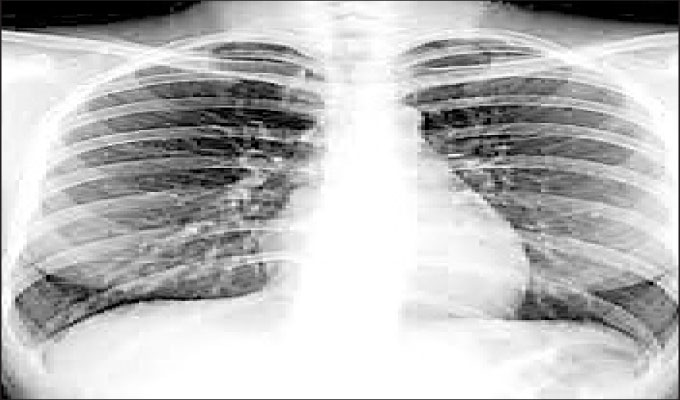

ନୂଆଦିଲ୍ଲୀ: ଆଜବେଷ୍ଟସ ସଂସ୍ପର୍ଶରେ ଦୀର୍ଘ ସମୟ ରହିଲେ ମଣିଷର ଫୁସଫୁସରେ ସଂକ୍ରମଣ ହେବା ସହ କ୍ଷତ ହୋଇ ଏଥିରୁ ରକ୍ତ କ୍ଷରଣ ହୋଇଥାଏ। ଏଭଳି ଶାରୀରିକ ସମସ୍ୟାକୁ ଡାକ୍ତରୀ ଭାଷାରେ ଆଜବେଷ୍ଟୋସିସ କୁହାଯାଏ। ଏହା ଯୋଗୁ ନିଶ୍ୱାସ ନେବାରେ କଷ୍ଟ ହେବା ସହିତ କାଶ, ଧଇଁ ପେଲିହେବା, ଛାତିରେ ଯନ୍ତ୍ରଣା ଆଦି ଲକ୍ଷଣ ଦେଖିବାକୁ ମିଳେ। ଏଭଳି ସମସ୍ୟା ଅଧିକ ଦିନ ଧରି ଲାଗି ରହିଲେ ଫୁସଫୁସ କର୍କଟ, ମେସୋଥେଲିଓମା, ପ୍ଲୁରାଲ ଫାଇବ୍ରୋସିସ, ହାର୍ଟ ସମସ୍ୟା ଆଦି ସୃଷ୍ଟି ହେବାର ଆଶଙ୍କା ଥାଏ।

ଆଜବେଷ୍ଟସ ଘରେ ବାସ କଲେ ଅବା ଆଜବେଷ୍ଟସ ତିଆରି ହେଉଥିବା ଶିଳ୍ପ ସଂସ୍ଥାରେ କାମ କଲେ ଏହି ସମସ୍ୟା ସୃଷ୍ଟି ହେବାର ଆଶଙ୍କା ଅଧିକ ରହିଥାଏ। ସମସ୍ତ ପ୍ରକାରର ଆଜବେଷ୍ଟସ ଯୋଗୁ ଏହି ସମସ୍ୟା ହୋଇଥାଏ। ଆଜବେଷ୍ଟସ ସଂସ୍ପର୍ଶରେ କେତେ ଦିନ ଧରି ସମ୍ପୃକ୍ତ ବ୍ୟକ୍ତି ରହିଛନ୍ତି ତାହା ଜାଣିବା ପରେ ଉପଯୁକ୍ତ ମେଡିକାଲ ଇମେଜିଙ୍ଗ କରି ସମସ୍ୟାକୁ ଚିହ୍ନଟ କରାଯାଏ।

ଏହା ଏକ ପ୍ରକାର ଇଣ୍ଟରସ୍ଟିସିଆଲ ପଲ୍ୟୁମୋନାରୀ ଫାଇବ୍ରୋସିସ ସମସ୍ୟା।